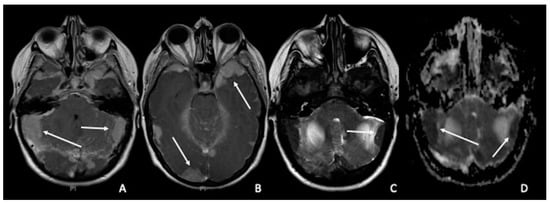

5. Medulloblastomas

2. Gliomas and Cellularity